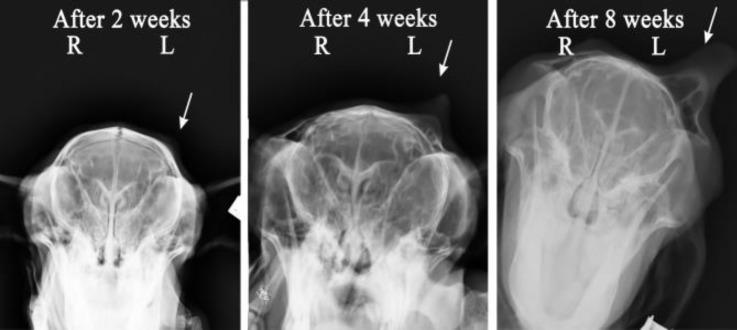

This study was conducted to evaluate the effect of subcutaneous administration of synthetic eugenol (EG) for disbudding of goat kids, as a new chemical method. Thirty apparently healthy Raieni (Cashmere) goat kids (five-day-old) were divided randomly into six groups (n = 5). In the pathology (P) groups (P, P and P according to the sample collection day after injection) an amount of 0.10 mL of EG was subcutaneously administrated in both horn buds. In the disbudding 1 and 2 (DB, DB) groups, 0.10 mL of EG, and in the control (C) group 0.10 mL normal saline was subcutaneously injected in the right horn buds, respectively. Eugenol injection in DB group was done in twelve-day-old goat kids. The left horn buds of DB, DB and C groups were considered as control of horn outgrowing. The horn buds, kidneys, liver, lung, brain and heart, tissue specimens were collected from P and P groups, and bud skin samples were collected from P group. The results showed that the EG was able to stop the horn growth in the first week of goat life. There was no significant difference between left and right horn size in the C group. Histopathological study revealed complete necrosis of bud tissue in dermal and epidermal layers, in P animals. Healing and re-epithelialization were seen in the samples taken from P group. Subcutaneous injection of the synthetic EG can be considered as a new method for goat kids disbudding.

本研究旨在评估皮下注射合成丁香酚(EG)作为一种新的化学方法用于摘除山羊羔角芽的效果。30只外观健康的拉伊尼(开士米)山羊羔(5日龄)被随机分为6组(每组n = 5)。在病理(P)组(根据注射后样本采集日分为P、P和P组),在两个角芽处皮下注射0.10 mL的EG。在去角1组和去角2组(DB1、DB2),分别在右角芽处皮下注射0.10 mL的EG,而在对照组(C组),在右角芽处皮下注射0.10 mL生理盐水。DB组在12日龄的山羊羔中进行丁香酚注射。DB1组、DB2组和C组的左角芽被视为角生长的对照。从P组和P组采集角芽、肾脏、肝脏、肺、脑和心脏的组织标本,从P组采集芽皮肤样本。结果表明,EG能够在山羊生命的第一周阻止角的生长。C组左右角大小之间无显著差异。组织病理学研究显示,P组动物的芽组织在真皮和表皮层出现完全坏死。从P组采集的样本可见愈合和重新上皮化。皮下注射合成EG可被视为一种摘除山羊羔角芽的新方法。